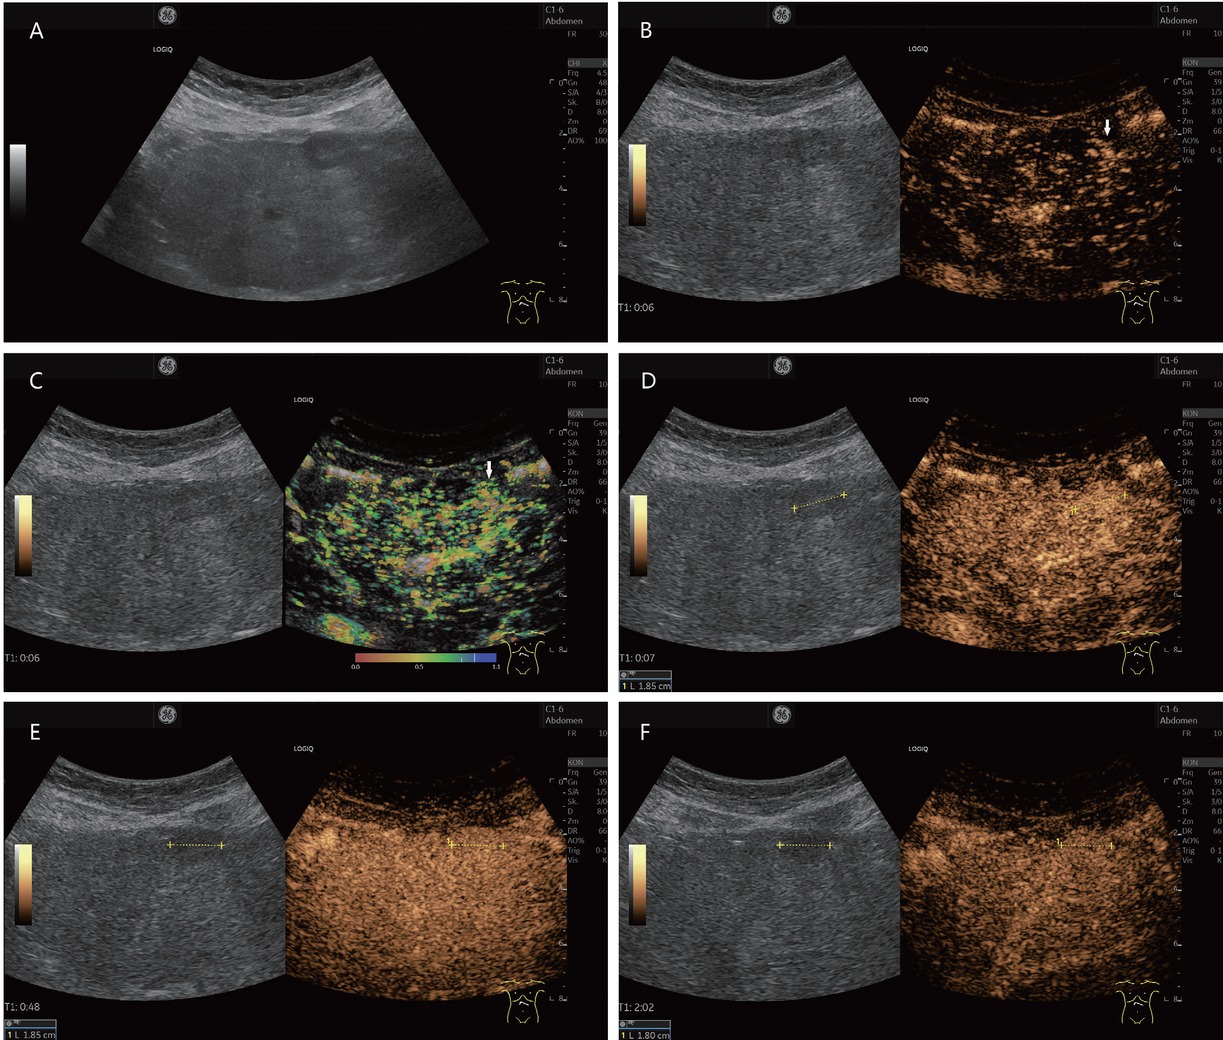

It is possible that with increasingly sensitive high-resolution modern imaging, more of these small FNH-like lesions could be detected in liver cirrhosis, but then also, they would be difficult to be differentiated (Figure 4).[69,71,73] As some FNH lesions (2/8, 25%) in cirrhotic liver in the study of D’Onofrio et al.[23] also showed hypoenhancement in the late phase on CEUS, differential diagnosis with HCC is very difficult in these lesions.[23] Also, in radiologic imaging with CT and MRI, 33% of FNH/FNH-like lesions in liver cirrhosis were misinterpreted as HCC.[74] One should consider the possibility of an FNH-like nodule and, in case of doubt, perform histologic confirmation. However, as the data of Choi et al.[74] show, histology by needle aspiration also does not provide definitive confirmation in all cases.[74] Table 6 summarizes the specifics of FNH.

A 38-year-old female presented with suspected FNH-like nodule, alcohol toxic cirrhosis (in between markers and shown by arrows). She had a history of continued alcohol abuse and had untreated hepatitis B and hepatitis C. She had undergone repeated hospitalizations with ascitic decompensation. Newly diagnosed hepatic lesion not present 6 months previously on B-mode ultrasonography (A). In CEUS, wheel spoke enhancement early arterial (B), corresponding temporal mapping also in parametric imaging (C). The lesion was enhanced in the arterial phase (D), isoenhanced or slightly hyperenhanced in the portal venous phase (E), and slightly hyperenhanced in the late phase (F). The lesion also remained iso- to slightly hyperenhanced in the further course of examination until 3 min p.i. MRI also showed an APHE hepatic lesion. The wheel spoke enhancement and persistent hyperenhancement on CEUS were suggestive of FNH. However, a corresponding lesion was not pre-documented. Therefore, sonographically assisted biopsy with 4× percutaneous access was performed. This did not result in a definitive diagnosis – no HCC, but also no FNH. The CEUS findings were compatible with an FNH. Since the lesion was not known before, it could be in the overall context with an FNH-like nodule. The contrasting course in the CEUS argues against a regenerated node. On further hospitalization with ascitic decompensation, the lesion remained unchanged and the AFP was normal even after 6 months. FNH: focal nodular hyperplasia; CEUS: contrast-enhanced ultrasonography; APHE: arterial phase hyperenhancement; HCC: hepatocellular carcinoma; MRI: magnetic resonance imaging; AFP: alpha-fetoprotein.